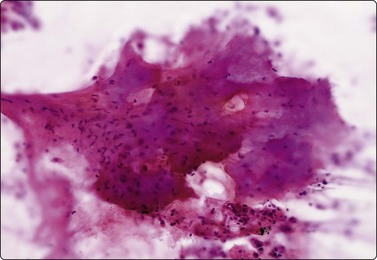

Fig. 8.2 Mesothelial cells

Monolayered sheet of cells showing ‘spongiotic’ separation of individual cells within the sheet (Pap, LP).

Mesothelium can be easily distinguished from bronchiolar epithelium. It is seen as various-sized, flat, monolayered sheets; there is usually more cell separation than in bronchiolar epithelium, which sometimes gives a sponge-like appearance. The cells appear to be joined by intercellular bridges similar to those of squamous epithelium in histological sections. (Fig. 8.2). Reactive mesothelium can appear atypical and be misinterpreted as neoplastic.